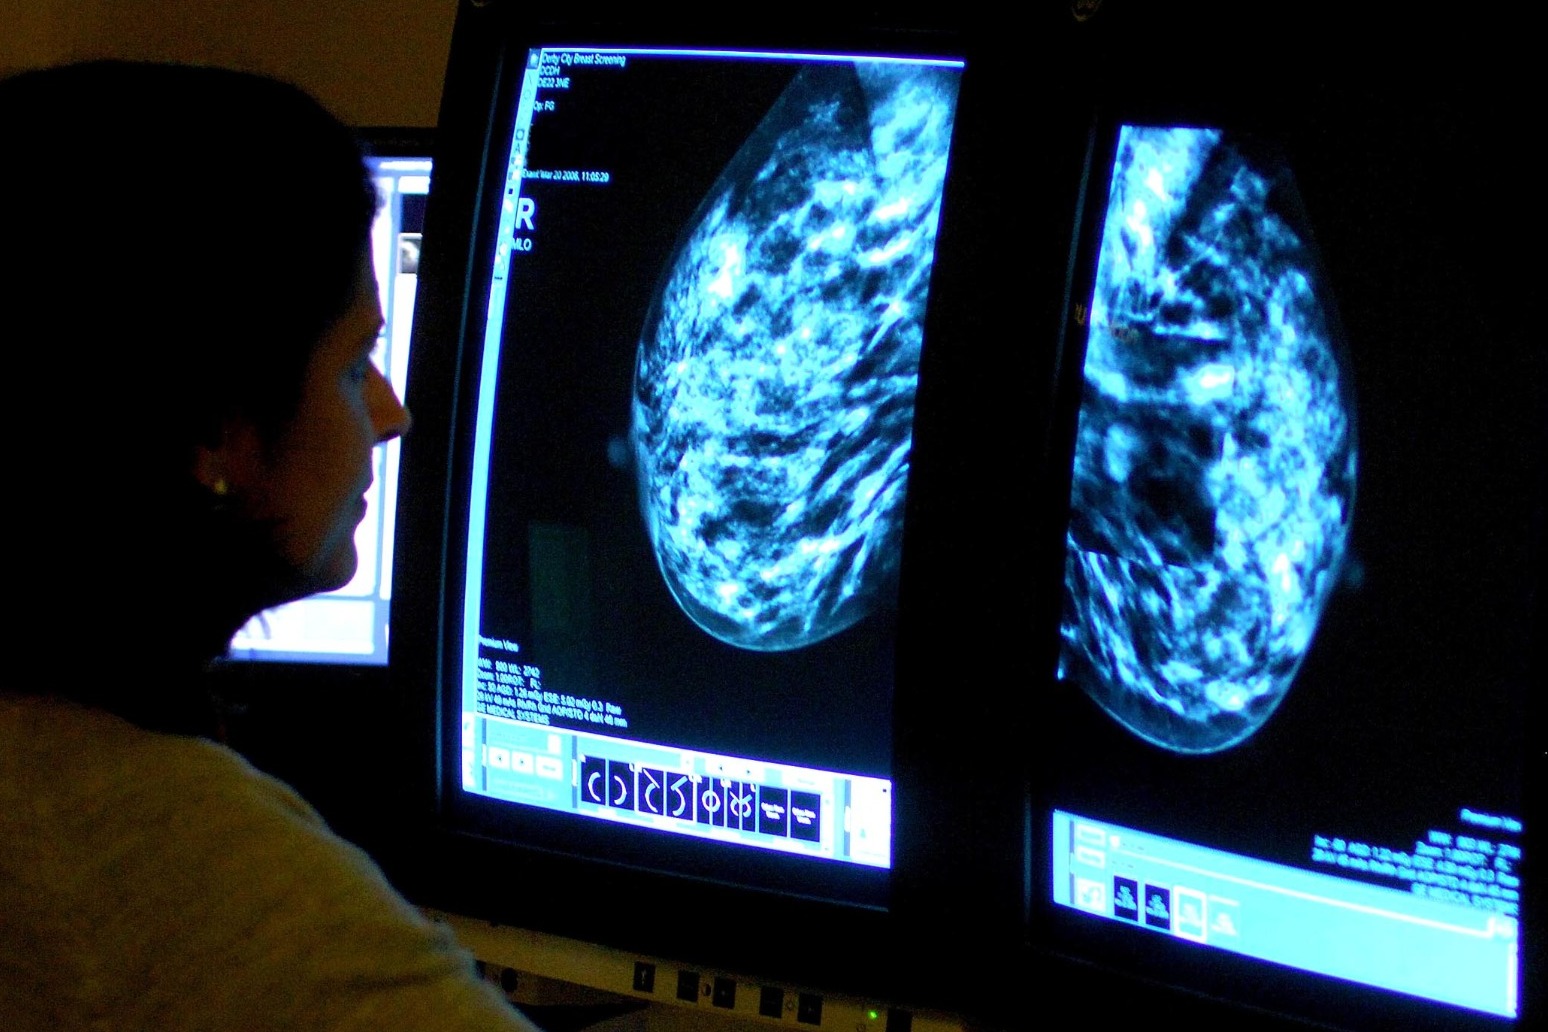

During the appointment, which usually takes about 30 minutes, two X-rays, known as mammograms, will be taken of each breast.